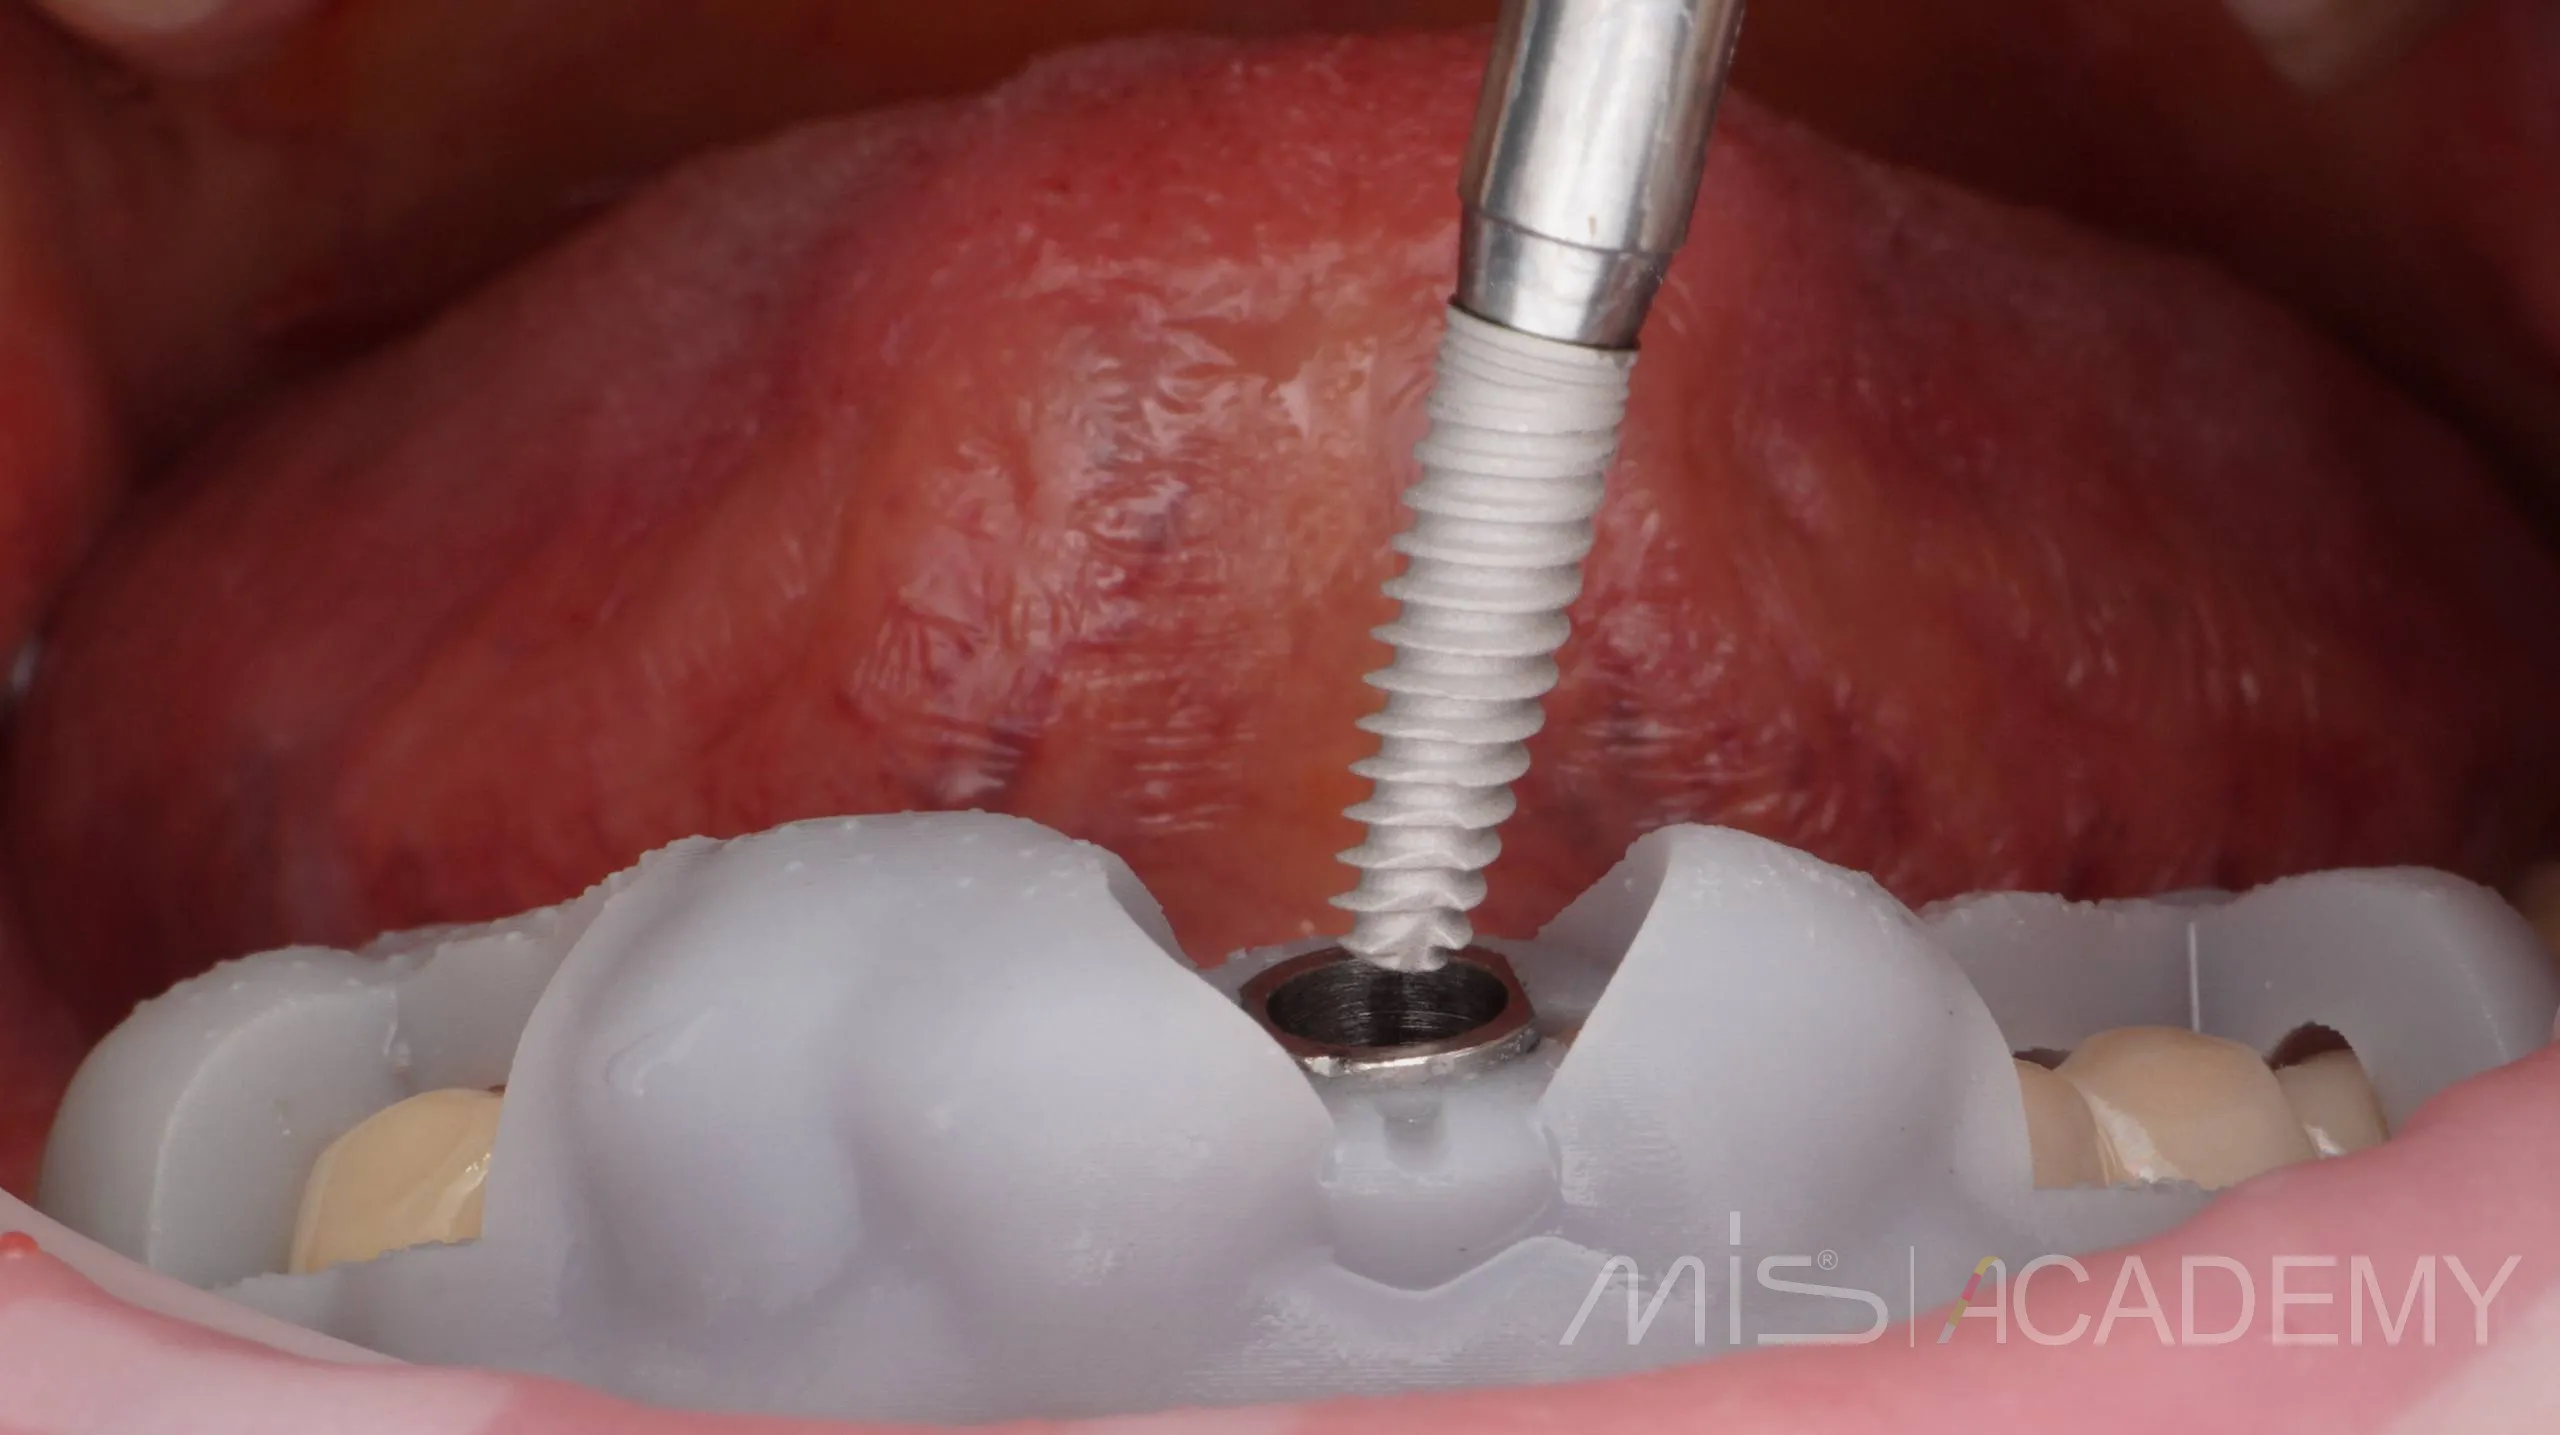

Одномоментная имплантация MIS С1

— Индивидуальный Zr формирователь десны на Connect абатменте